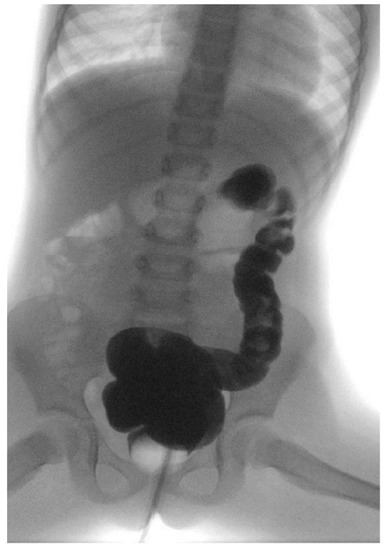

- Volumetric enema: simulation of TAI under fluoroscopy in order to evaluate the volume of water (contrast) needed to opacify the entire left colon and the volume (number of puffs) of the rectal catheter needed to obtain the adhesion of the balloon to rectum walls without water leak during the procedure and without pain during and after insufflation.